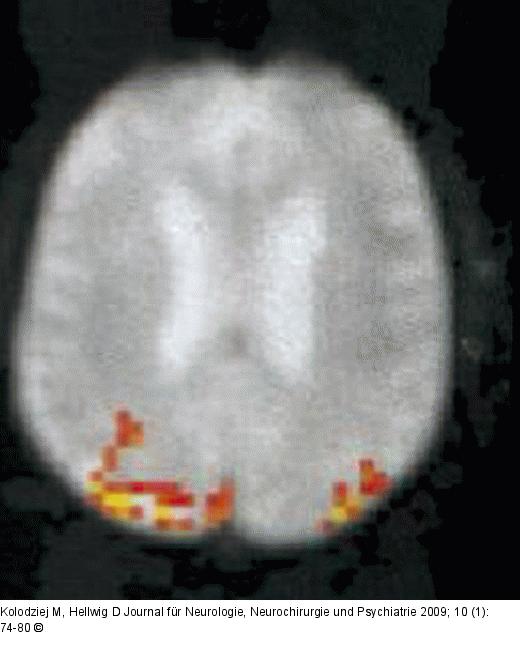

Abbildung 2: Motorcortex Motorcortex in f-MRT |